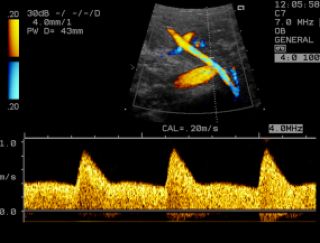

Mittels dieser Untersuchung werden Blutflußmuster in mütterlichen und kindlichen Blutgefäßen mit einer speziellen Ultraschalltechnik dargestellt.

Durch die Beurteilung der Blutflussmuster in den Gebärmutterarterien kann ein erhöhtes Risiko bezüglich einer Mangelversorgung des Feten (Plazentainsuffizienz) oder einer Präeklampsie (schwangerschaftsbedingter Bluthochdruck und Eiweißausscheidung im Urin) bereits zwischen der 20. -24. Schwangerschaftswoche erkannt werden. In diesem Fall kann eine intensivierte Überwachung der Schwangerschaft notwendig sein.

Nabelschnurarterie

Durch die Messung der kindlichen Blutflüsse in Arterien und Venen kann die Versorgung des Feten beurteilt werden. Insbesondere bei einer kindlichen Mangelentwicklung kann durch diese Untersuchungsmethode eine effektive Überwachung des Kindes gewährleistet werden. Auffällige Blutflussmuster können Hinweise auf eine kindliche Gefährdung sein, die eine vorzeitige Entbindung nötig machen.

- in den Gefäßen der Gebärmutter zur Abschätzung des Risikos einer kindlichen Mangelversorgung und/ oder Präeklampsie jenseits der 20. SSW

- als Kontrolluntersuchung in der 28.-30. SSW bei allen Schwangeren mit erhöhtem Risiko für die Entwicklung einer Präeklampsie oder kindlichen Mangelentwicklung

- in den kindlichen Gefäßen ab der 14. SSW

- individuell in Abhängigkeit vom Ausmaß der kindlichen Mangelversorgung bei Risikoschwangeren